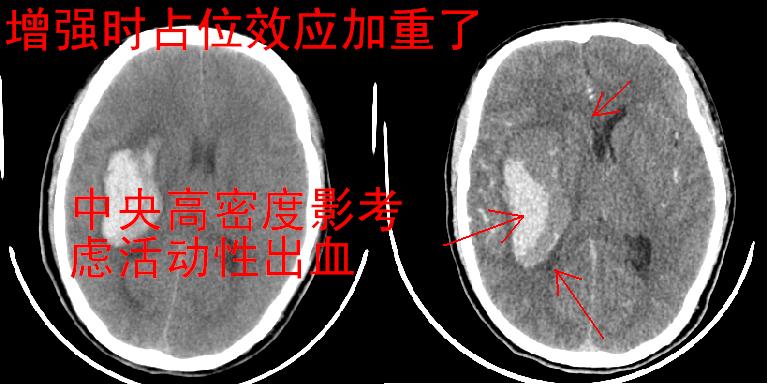

考虑高血压性脑出血,依据:

1是高血压性脑出血的好发部位,形态呈肾形,是高血压性脑出血的常见形状

2增强时占位效应加重了,考虑出血还没有停止

3病灶周围水肿不是太厉害,一般肿瘤出血水肿多非常明显

4病灶周围的‘软组织’影没有明显的强化

5至于脑血管畸形引起的出血,暂时没有看到明显的畸形血管影,也不太支持

另附部分资料:“血液溢出血管外形成血肿,其内含有大量血红蛋白、血浆白蛋白,球蛋白,因这些蛋白对x线的吸收系数高于脑质,故ct呈现高密度阴影,ct值达40~90h,最初高密度灶呈非均匀一致性,中心密度更高,新鲜出血灶边缘不清。基底节区血肿多为“肾”型,内侧凹陷,外侧膨隆,因外侧裂阻力较小,故向外凸,其它部位血肿多呈尖圆形或不规则形”